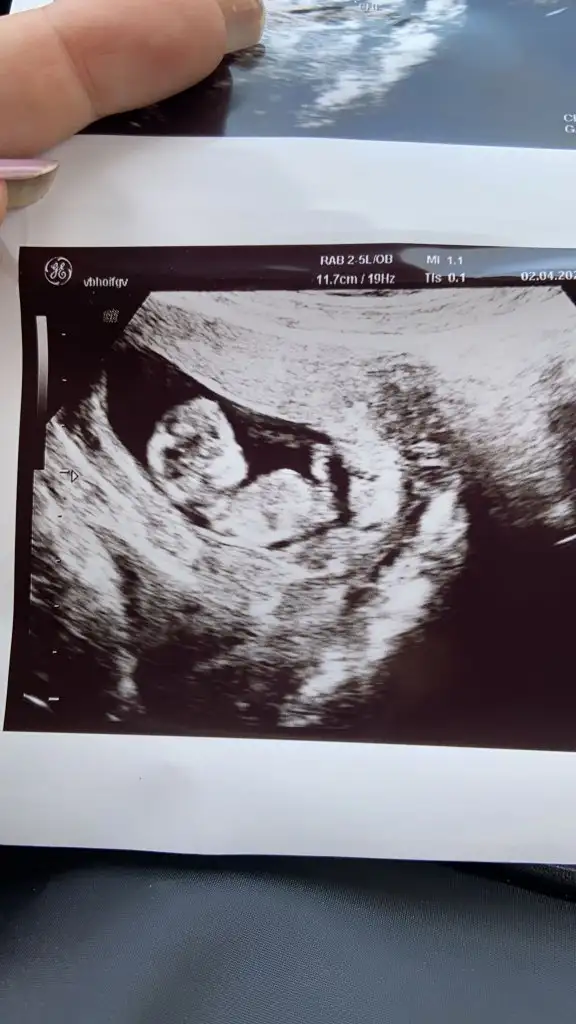

Kızlar 17 haftalık gebeyım Dr ilk erkek dedi 11+6günluk ıken şimdi kız dedı resim paylaşıyorum 11+6gunlukken

Benım gıbı olan var mı